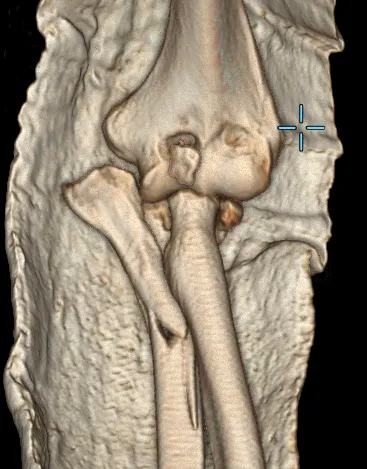

左肘关节CT平扫+三维检查提示

左肘关节面对位欠佳

左尺骨鹰嘴及桡骨头骨折

周围软组织肿胀

图片